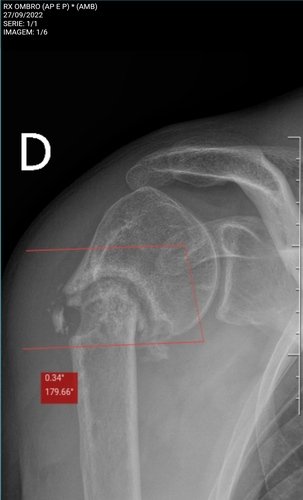

Meu namorado foi atingido por uma carro em 2020 e fraturou o úmero superior direito, fez cirurgia e colocou fios de Kirschner, fez fisioterapia mas nunca chegou a ficar 100%. Perdendo 75% da movimentação do braço! Após novo trauma no braço descobriu que a fratura nunca colou / nunca se consolidou, criando pseudoartrose, agora precisando fazer uma nova cirurgia e por uma placa, algo que não é contemplado pelo SUS / Sistema Único de Saúde. Ele não consegue trabalhar e se manter, sente dor e a movimentação está menor do que antes! O mesmo precisará entrar na justiça, sabemos como isso é demorado. Então pretendemos fazer particular. A cirurgia tem um custo estimado em 30 mil reais! Toda ajuda será bem vinda!

Cid M84.1